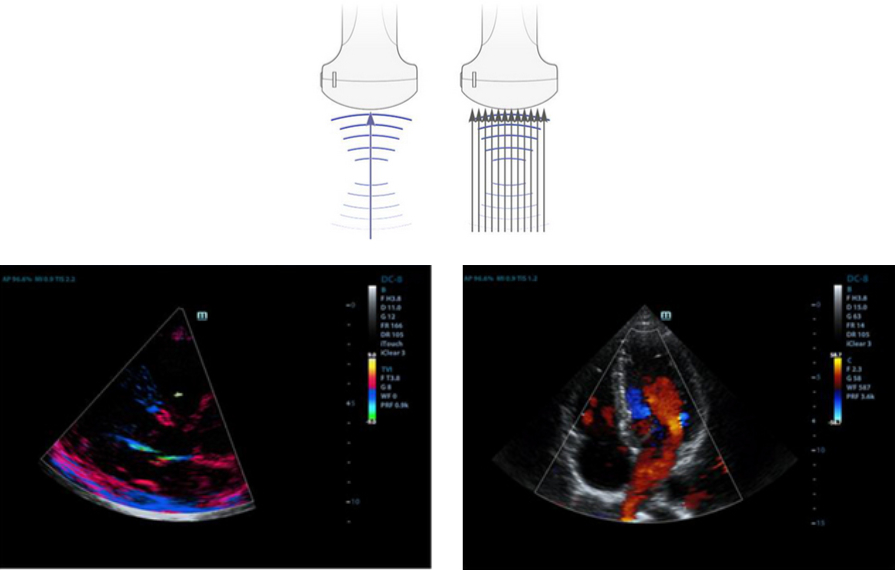

Multi-Beam Formation

Up to 12 beams can be transmitted at once, resulting in excellent time resolution and higher frame rate.

iClear

Gain improved image quality based on auto structure detection.

- Sharper and continuous edges

- Smooth uniform tissues

- Cleaner ŌĆśno echo areasŌĆÖ

iBeam?

Use multiple scanned angles to form a single image for enhanced contrast resolution and improved visualisation.